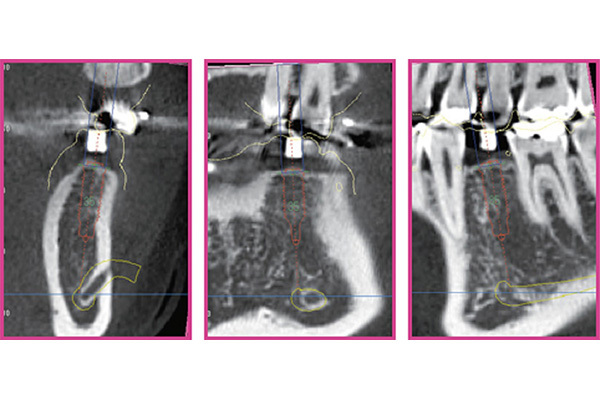

難症例でもインプラント治療を成功させるために、当院では最新のインプラントシュミレーションソフトiCATを用いてより精密な分析を行っています。

撮影させて頂いたCTを当院が導入している分析ソフトiCATを用いて、CTで得られた情報を3D化します。

構成された仮想空間にインプラントを仮置きして、シミュレーションすることによって、どの位置にインプラントを埋入すれば最適なのかを判断出来ます。

難症例でもインプラント治療を成功させるために当院では最新のインプラントシュミレーションソフトicatを用いてより精密な分析を行っています。

世界ではじめてicatシステムが可能にした「インプラント断面」により精度の高いインプラントシミュレーションを実現